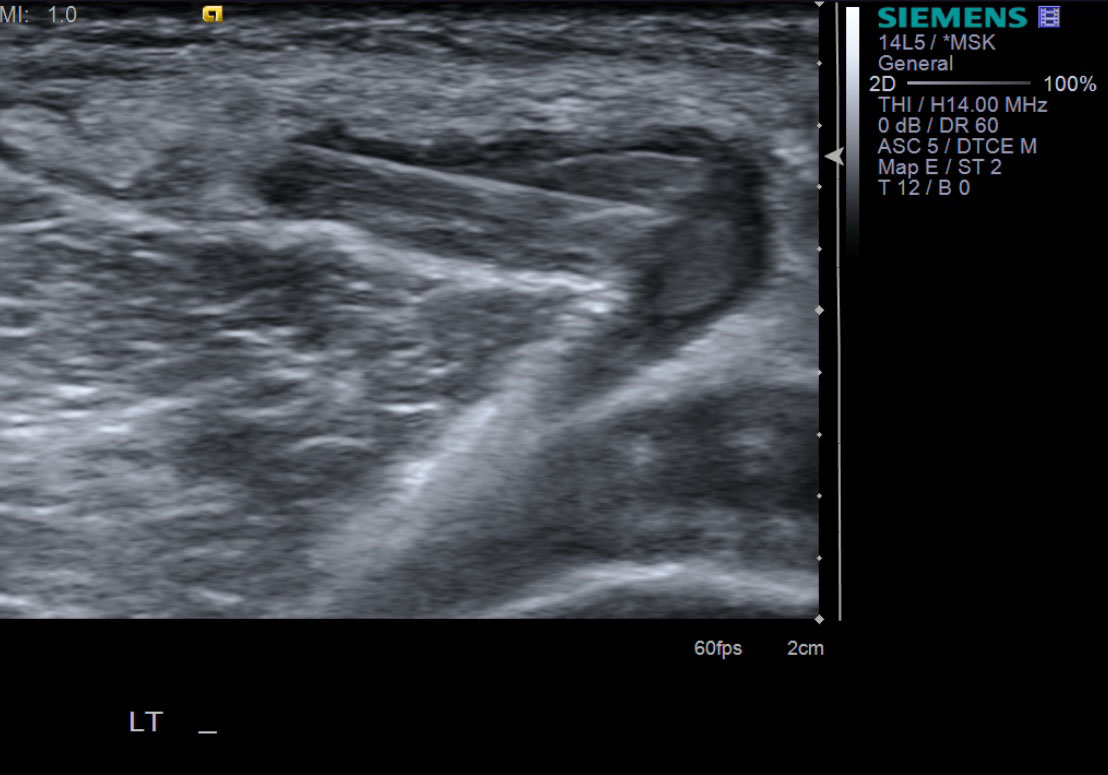

• probe: 14Mhz or 9Mhz depending on patient body habitus

2. Position patient prone. Picture of probe on patient when prone

3. Pre-procedure images to identify optimal path. Ideally, place probe in transverse plane.

• descriptiondescription

10. With ultrasound guidance, advance the 18g needle into the Baker's cyst.